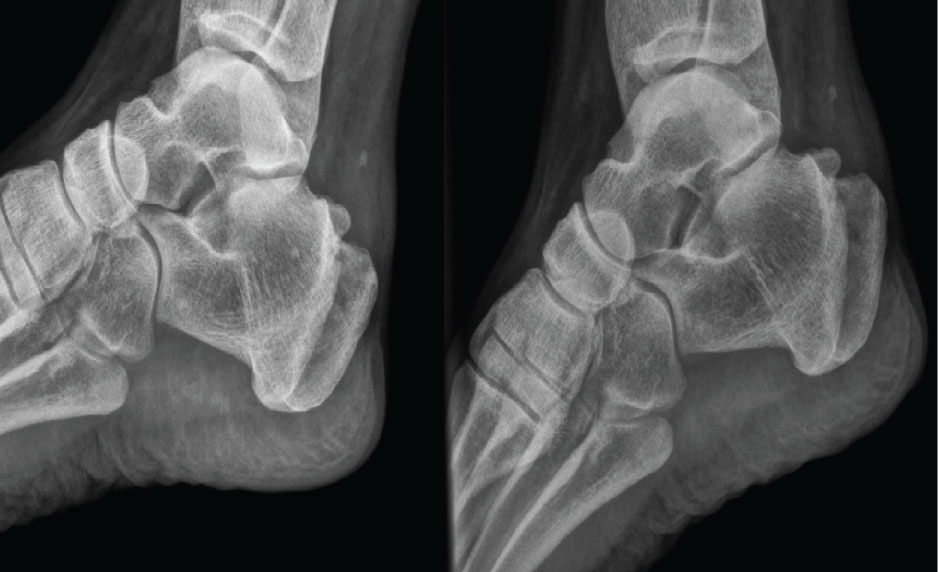

With regard to the change in millimeters (mm) of the calcification, all of the patients showed a decrease in the size of calcification. The radiological change in Achilles CT was significant; decreased from 10 ± 5.3 to 5.3 ± 5.22 mm (p = 0.0186), (Table 2, Figures 2, Figure 3, Figure 4, Figure 5 and Figure 6).

Figure 2: Case 1: In a 50-year-old female, after 10 sessions of treatment, pain decreased from 8/10 to 1/10 and size of calcification decreased from 12 to 6 mm. View Figure 2

Figure 3: Case 2: In a 38-year-old female, after 20 sessions of treatment, pain decreased from 10/10 to 2/10 and size of calcification decreased from 3 to 2 mm. View Figure 3

Figure 4: Case 3: In a 47-year-old male, after 20 sessions of treatment, pain decreased from 7/10 to 4/10 and size of calcification decreased from 10 to 0 mm. View Figure 4

Figure 5: Case 4: In a 57-year-old female, after 15 sessions of treatment, pain decreased from 9/10 to 4/10 and size of calcification decreased from 9 to 4 mm, evaluated by sonography. View Figure 5

Figure 6: Case 5: In a 57-year-old female, after 15 sessions of treatment, pain decreased from 5/10 to 0/10 and size of calcification decreased from 6 to 0 mm, evaluated by sonography. View Figure 6